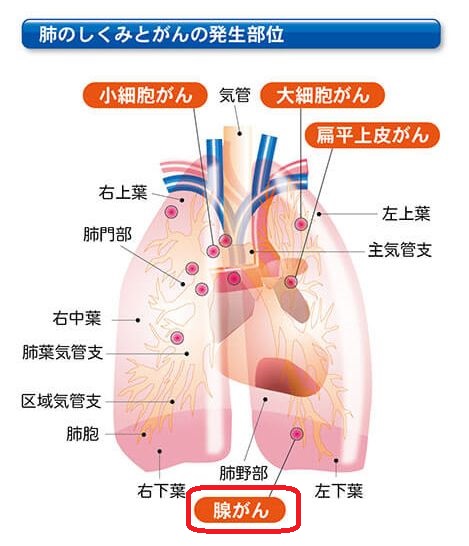

膵臓がんの脳転移 症状 診断 治療 余命および特徴的な遺伝子異常と

小細胞肺がんの治療 限局型の治療の進め方は 進展型の治療の進め方は